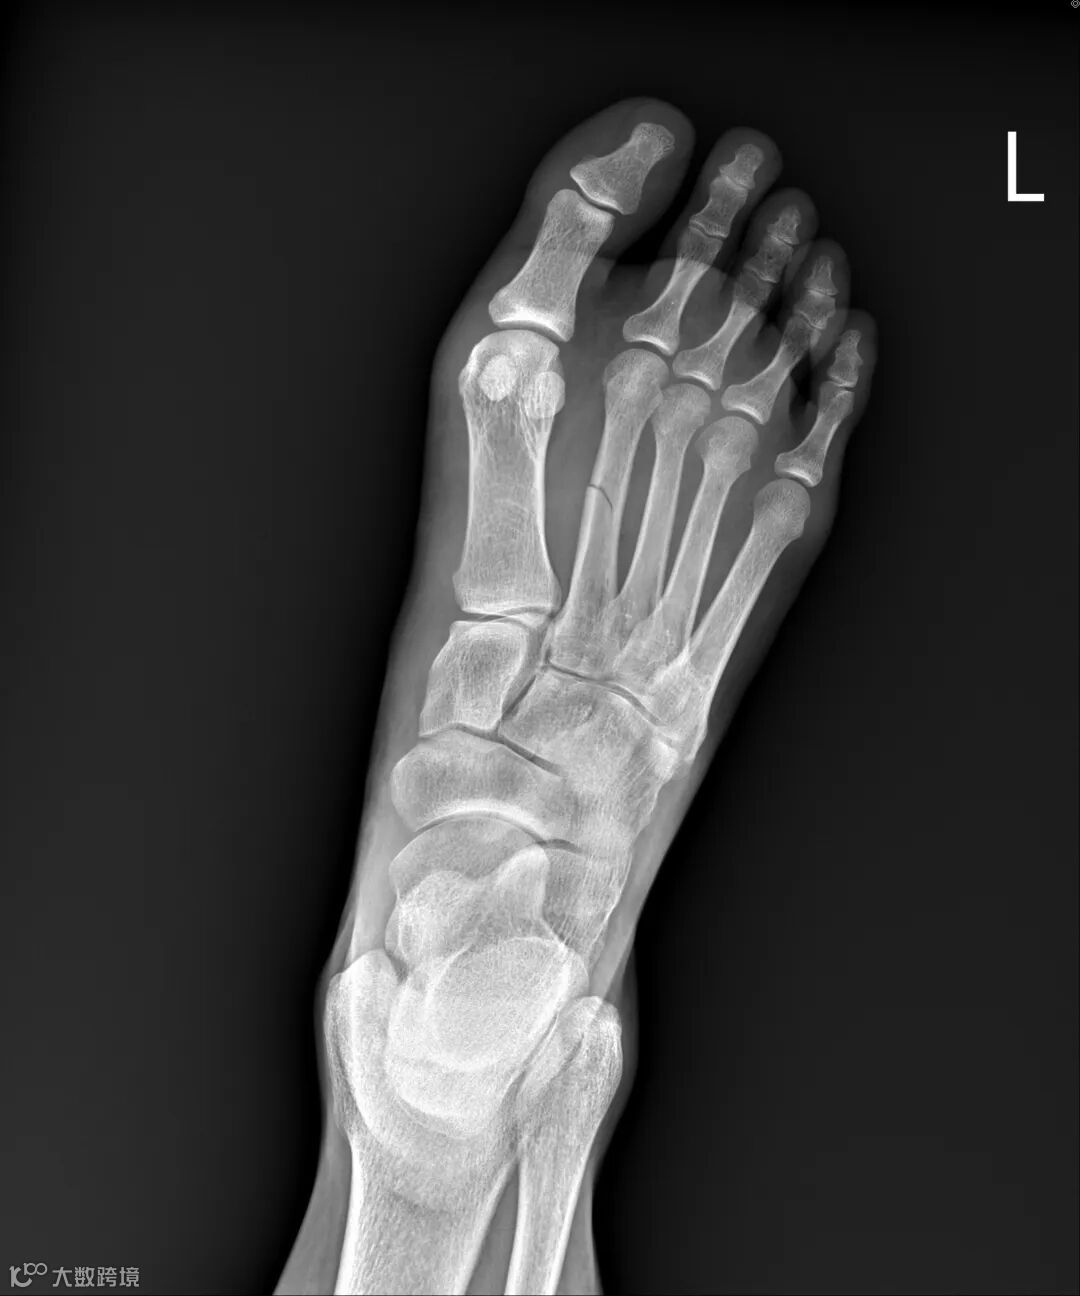

姐姐国中同学刚好是骨科住院医生,特地过来关心,耐心地说明目前伤势,除了已知的小腿骨折外,他指着脚背说,这里也有骨折。

我马上说出骨头学名:跖骨,因为同一只脚第四根有断过。

那是我人生第一次骨折,发生在峇里岛第一高峰阿贡火山下山路上,在一碎石与火山灰混合区滑倒,左脚掌肿痛,只能慢慢蹭下山。到当地医院检查,医生说没有骨折,只是扭伤。自我评估伤势还在忍耐范围内,几天后如期参加马拉松赛事,靠着路上“PUSH YOUR LIMIT”标语熬完跑半马。两周后肿胀状况并没有好转,回台就医才知道是骨折了。之后的几年,只要天气一变化,它便开始隐隐作痛。